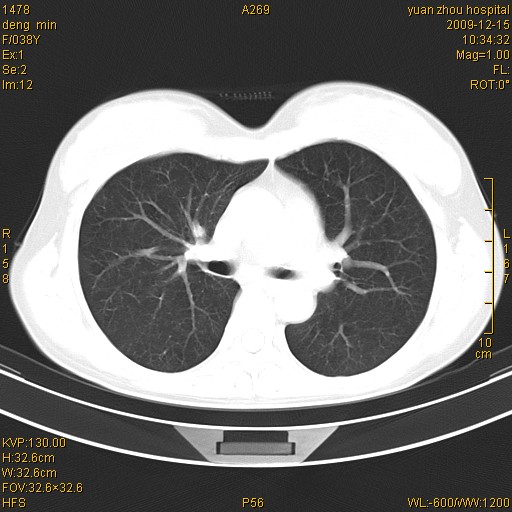

标题: CT23919:F38Y 咳嗽月余 [打印本页]

标题: CT23919:F38Y 咳嗽月余

支气管扩张。典型。

右肺中下叶、左肺上叶舌段及左肺下叶支气管扩张合并感染。